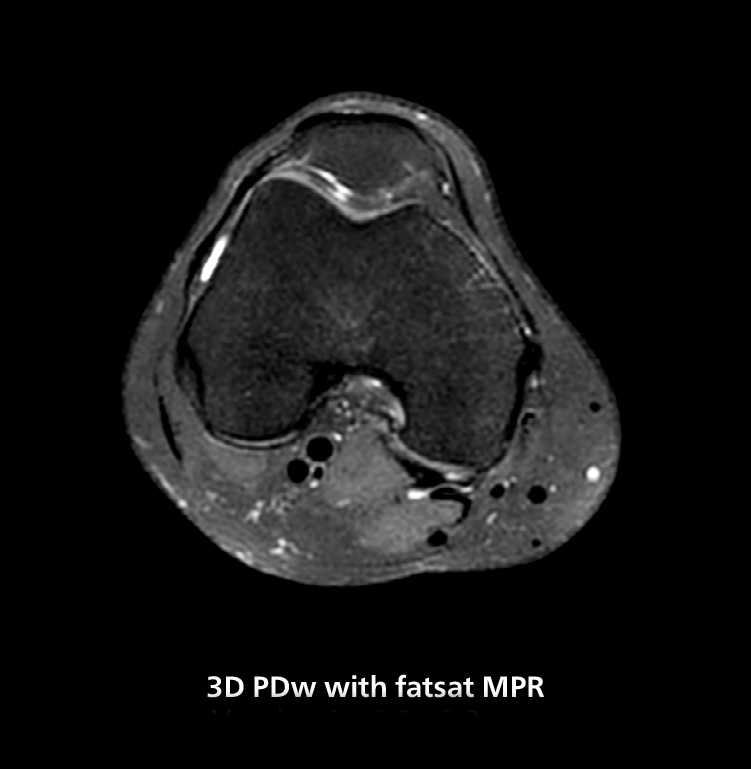

3D knee imaging

The isotropic high resolution 3D sequence in this MRI case allows for reformatting to obtain other orientations with high quality. Acquired on the MR 5300 system.

“We have more speed in 3D sequences,” Dr. Gellée states. “With Compressed SENSE, we can replace two or three 2D scans withone high-quality 3D scan. High quality additional orientations are then obtained by post-processing of the 3D data set, thus saving scanning time.”